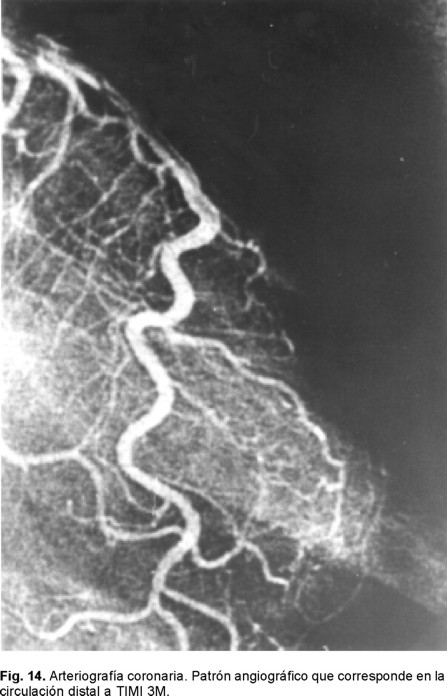

Lo más trascendente es que nos obliga a abrir la mente en aspectos terapéuticos que antes no se consideraban relevantes en la clínica. Tal es el caso al referirnos a los procedimientos más utilizados hoy día para resolver la problemática de arterias epicárdicas ocluidas en el infarto agudo del miocardio o parcialmente obliteradas como en la angina inestable. Si bien la primera meta de la reperfusión en el IAM ha sido obtener flujo TIMI - 3 epicárdico, ésta no parece ser hoy día el solo punto terapéutico final deseado.111 Ya que lo que es óptimo es alcanzar también una perfusión normal a nivel miocárdico y que incluye como premisa la permeabilidad completa de la microcirculación, para entonces decir que se alcanzó flujo TIMI - 4 o miocárdico. Ésta es una de las razones por la que con los métodos modernos de reperfusión no es posible reducir la mortalidad del IAM a cifras cercanas al cero. Con los comentarios hechos previamente también queda claro que hay otros aspectos que están vinculados a la propia reperfusión: el daño ocasionado por ésta, el fenómeno de no flujo, el miocardio aturdido, el hibernante y aspectos aún desconocidos como es la consecuencia de liberar la propia obstrucción microvascular. Patologías isquémicas que tienen un punto inicial de partida: la placa aterosclerosa vulnerable que sufre erosión o fractura (Fig. 4). Situación que deja expuesta la matriz subendotelial y en donde su principal contenido de masa oclusiva es la plaqueta [trombo blanco], mas hay trombosis también donde predominan los glóbulos rojos, con oclusión completa o subtotal en un proceso no estático en sus componentes y que a su vez da origen a los síndromes coronarios agudos de infarto con o sin elevación del segmento ST.109 Es así como en su evolución se ha identificado el fenómeno de la microembolización con alojamiento de estos fragmentos plaquetarios y del contenido de la matriz en los microvasos coronarios distales, proceso que antes se consideraba como una condición no frecuente. Este mecanismo se ha vinculado como una de las posibles causas por la que se generan arritmias y es causa de episodios de muerte súbita.107,108 Es de llamar la atención que no hay muchos estudios importantes donde el área histológica relacionada con el infarto se ha investigado sistemáticamente en el post mortem de estos sujetos. Aspecto que se puede considerar como una deficiencia en nuestros conocimientos actuales, particularmente cuando la terapia trombolítica o la de reperfusión de la ARI con catéteres son nuestros principales métodos terapéuticos para la atención del IAM y ambos son capaces de promover la embolización (Fig. 5). Los PCI se iniciaron hace más de dos décadas y durante todo este tiempo hemos subestimado la posibilidad de que esta situación patológica o bien se le ha considerado muy rara o sólo era conferida al terreno de los injertos de safena añosos y degenerados cuando éstos eran manipulados con catéteres.112 Porqué no nos hemos hecho la pregunta antes: ¿qué sucede con el material de la placa ateromatosa al ser instrumentada? En realidad es hasta hace poco que la opinión de lo raro o lo frecuente de la posibilidad de embolización a la microcirculación ha sido posible contestarla y poder decir si en realidad esta situación derivada del manejo medicamentoso farmacológico o del intervencionismo es trascendente, o bien es irrelevante.

Sabemos que hace 70 años la mortalidad del IAM era cercana al 40%, misma que se logró reducir al 25% a principios de 1951 con la simple maniobra de la movilización temprana y al 20% con la creación de las Unidades Coronarias en 1973. Es en 1987, con la introducción de la terapia fibrinolítica que se establece un nuevo descenso para considerarse cercana al 8%. Ya perfeccionada la terapia de reperfusión y con la introducción de los PCI (angioplastía con balón y mallas endovasculares coronarias) es que tenemos un resultado que oscila del 4 al 6% de mortalidad del IAM (Fig. 10). Es por eso que hoy día se acepta que esta modalidad terapéutica es la que ha sido capaz de brindar el más importante descenso de la mortalidad en el rubro del IAM transmural. Entre los factores más importantes de los que depende alcanzar esta reducción está el factor tiempo relacionado al momento en el que se de el tratamiento o ventana terapéutica en la que se aplique la terapia de reperfusión. La magnitud de miocardio salvado determinada experimentalmente para el ventrículo izquierdo es cercano al 70% si la reperfusión se realiza en la primera hora a partir de haberse ocluido la arteria epicárdica. Disminuye al 40% a la tercera y al 20% a la sexta, para ser menor del 5% a las 24 horas. Para el ventrículo derecho Lester y colaboradores124 han encontrado que el área de infarto a la hora de reperfusión es de tan sólo un cinco por ciento, a las cuatro horas es de un 10% y a las ocho es del 20%. Por lo tanto, el acortar el tiempo de la reperfusión para cualquiera de ambas cámaras ventriculares sería igual a menor daño miocárdico o mayor magnitud de miocardio salvado. Esta es una de las razones por la que después de seis horas el beneficio de la reperfusión de la arteria epicárdica decae significativamente para considerarla casi nula después de doce horas. Lo que se aplica tanto para el tratamiento fibrinolítico como para los PCI. Si en la ARI no se obtiene permeabilidad inmediata la mortalidad es del 17.5%, lo que equivale a remontarnos a la consignada en los años de 1970. Si la ARI está permeable a los 90 minutos pero se le encuentra ocluida al séptimo día, la mortalidad es del 12% lo cual nos ubica en la mortalidad documentada a principios de 1980. Si la ARI está permeable a los 90 minutos y al séptimo día la mortalidad es del 4.7%. Por otro lado, la importancia de la calidad del flujo epicárdico post reperfusión resulta extraordinariamente relevante. Las primeras observaciones en este sentido con la terapia de reperfusión lítica nos demostraron que cuando el flujo epicárdico es TIMI: 0 -1 la mortalidad del IAM es del 8.9%, al ser grado TIMI: 2 la mortalidad es del 7.4% y con TIMI: 3 epicárdico es del 4.4% (Figs. 8 y 11 A - 11 B). Pero por fortuna hemos avanzado en el conocimiento en este sentido y con la valiosa información del estudio GUSTO II b (The Global Use of Strategies to open Occluded Coronary Arteries in Acute Coronary Syndromes) sabemos que con ACTP de obtenerse flujo TIMI 0-1-2 la mortalidad es del 18 - 20%, cifras que resultan casi del doble de las documentadas con trombólisis para los mismos flujos, hecho interesante que nunca se ha explicado claramente.125 En cambio de obtenerse flujo TIMI 3E la mortalidad a treinta días es de tan sólo 1.6%, observándose menor tamaño del área infartada y mayor índice de miocardio salvado. Lo que establece sólo una diferencia del 2.8% entre las dos estrategias de reperfusión cuando se alcanzan flujos TIMI 3E (Fig. 8). Para llegar a estas conclusiones, frente a los enfermos es menester tomar en consideración los datos relevantes proporcionados por Gibson y colaboradores en relación al análisis angiográfico de la perfusión miocárdica.126 Mismo que se ha valorado por dos métodos pero que al final sólo traducen que existe perfusión a nivel de la microvasculatura. Empero hay que recordar que existen varios factores de los que también depende el flujo TIMI epicárdico como son los de orden: hemodinámico, la anatomía local de la arteria, la propia técnica del procedimiento, el trombo intracoronario y aspectos derivados del intervencionismo: la estenosis residual, la disección involuntaria de la arteria coronaria y menos relevantes parecen la aplicación de las mallas endocoronarias (Fig. 12).126 Excluidas estas causales, quedarían las dos más importantes a considerar: la obstrucción microvascular y las que son producto del fenómeno de no flujo en la microcirculación. El flujo TIMI en la microcirculación se expresa o se visualiza en la angiografía coronaria como áreas de condensación de aspecto esmerilado muy finas del material de contraste a nivel del miocardio. Esto es lo que los autores anglosajones designan en su lengua como "blush" y que correspondería a "TIMI miocárdico 4".127-130 Si bien las anomalías de la microcirculación se han demostrado de manera fehaciente por los diferentes métodos citados con antelación, si se cuestiona si lo que documentamos es también producto de edema miocárdico y/o del daño por reperfusión. Sin embargo este patrón de alteración microcirculatoria ocurre tempranamente (en las primeras horas o días), lo que hace menos probable que sea por daño por reperfusión. Es más, se le ha documentado en sujetos que van a PCI (rotaablación coronaria) y tras la práctica de ellos aparecen cambios miocárdicos en los estudios de perfusión nuclear, lo que sugiere embolización a la microcirculación (Fig. 13). 121,122 Con la utilización de catéteres con redes o sistemas de aspiración se han recuperado fragmentos del material que hubiesen sido embolizados. Por lo tanto, en la clínica se puede decir que este mecanismo se sugiere como la causa primordial, al menos en etapas tempranas, de las anomalías documentadas en la microcirculación. Mas es innegable que en el caso de IAM transmural reperfundido deberán estar presentes los dos mecanismos, el inicial ligado a la microembolización y el tardío aunado a los fenómenos de la injuria post reperfusión (Fig. 5). Lo importante es que la obstrucción microvascular está vinculada a mal pronóstico aún de obtenerse la permeabilidad deseada de la arteria epicárdica. Wu y colaboradores131 han demostrado que a 25 meses el 90% de los enfermos sin OMV están libres de muerte-reinfarto e insuficiencia cardiaca. De existir OMV tan sólo el 55% lo estarán. Es más, con estudios de resonancia magnética nuclear se ha podido catalogar la magnitud de los defectos en áreas grandes, moderadas y pequeñas de OMV con diferencias estadísticas en morbimortalidad de cada una de estos grupos y directamente proporcionales a la magnitud del defecto documentado en la resonancia magnética nuclear. Uno de los primeros estudios en llamar la atención en la posibilidad de microembolización ligada a PCI fue el CAVEAT (Coronary Angioplasty Versus Excisional Atherectomy) donde la incidencia de IAM fue superior a la esperada. Se encontró una frecuencia de IAM del 3% para ACPT y del 6% para aterectomía rotacional. En este estudio prospectivo la elevación de la CK-MB a cifras tres veces por arriba del valor basal fue de 8% para la ACTP y del 19% para la aterectomía.121 En el estudio CAVEAT II sobre intervenciones en libramientos de venas safenas la incidencia de IAM fue considerablemente mayor 15 y 24% respectivamente.122 En nuestro medio Vallejo E y colaboradores132 revisaron 204 angioplastías electivas y 62 primarias. El fenómeno de no flujo predominó en hombres, con edad promedio de 56 años y fue la diabetes mellitus un factor de mayor riesgo para observarlo. La incidencia global del problema fue del 5.2%, 16.1% para la angioplastía primaria y del 1.9% en los procedimientos intervencionistas electivos. Por lo tanto, los autores no la consideran como una complicación rara o infrecuente particularmente en el escenario del IAM. Este importante hallazgo de todos los estudios previamente mencionados dio origen a ciertos debates, si los procedimientos intervencionistas utilizados creaban fuga enzimática, eran capaces de dar seudoinfartos o microinfartos.66 En el seguimiento a largo plazo se demostró un exceso de mortalidad para la aterectomía y aquellos que fallecieron presentaron durante el procedimiento cambios dinámicos del segmento ST muy sugestivos de IAM no transmural o subendocárdico. Varios estudios posteriores han demostrado que a mayor elevación de la CK-MB post PCI hay mayor probabilidad de muerte.121,122 Así cuando la elevación de CK-MB es de cinco veces el valor basal, la mortalidad al año es de 6 -7%, de ser 10 veces el incremento de CK-MB es del 13%. La posible causa de este hallazgo es la microembolización coronaria ya que otras eventualidades son menos frecuentes o resultan menos probables como factores causales tales como el tiempo de isquemia ocasionado por el balón que es habitualmente demasiado corto para ocasionar necrosis per se. Las oclusiones abruptas de ramas coronarias epicárdicas hoy día son poco frecuentes (< 3%) y la oclusión sú bita coronaria transitoria se le ve en menos del 1%.135 La incidencia por lo tanto de grados diversos de micromionecrosis, consecuencia de la embolización coronaria, al menos significativa no parece despreciable. Valorada utilizando biomarcadores como la Troponina T o I parece cercana al 30 - 40%. Si bien la identificación alta de troponinas post intervención parece importante, también lo es cuando se documentan elevaciones de la misma antes de realizar los PCI.136,137 Así Hamm y cols138 han demostrado que hay una respuesta diferente al tratamiento con bloqueadores de los receptores plaquetarios. Aquellos con Troponina T positiva al ingreso responden favorablemente al inhibidor del receptor plaquetario por el bloqueo del mecanismo citado a nivel de la microcirculación, además de reducir la frecuencia del trombo en la arteria epicárdica sometida a ACTP o a la colocación del stent.